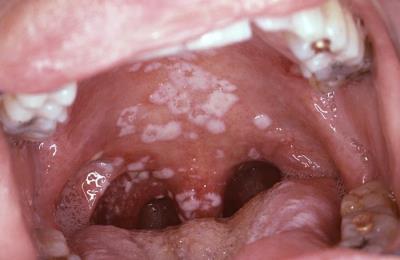

Прежде чем назначать лечение, доктор должен установить причину появления таких симптомов. В зависимости от причин налет может иметь разный вид:

комочки белой творожистой массы на гландах;

- светлый налет с неприятным запахом изо рта;

- пятна на миндалине и на щеке с одной стороны;

- белая пленка на стенках горла и щек.

Существует масса видов проявлений белой пленки в горле. В зависимости от локализации, интенсивности цвета и ее структуры можно выделить болезни, которые спровоцировали подобные признаки.

Кандидоз или молочница – как ее именуют в народе, появляется в виде светлой пленки из грибков кандиды. Часто болезнь сопровождается затхлым запахом, першением в горле.

Врачи отмечают, что белый налет на гландах может быть признаком различных заболеваний, включая ангину, хронический тонзиллит и грибковые инфекции. Основные причины его появления связаны с инфекциями, которые вызывают воспаление и отек тканей. Важно учитывать, что налет может сопровождаться другими симптомами, такими как боль в горле, затрудненное глотание и повышение температуры.